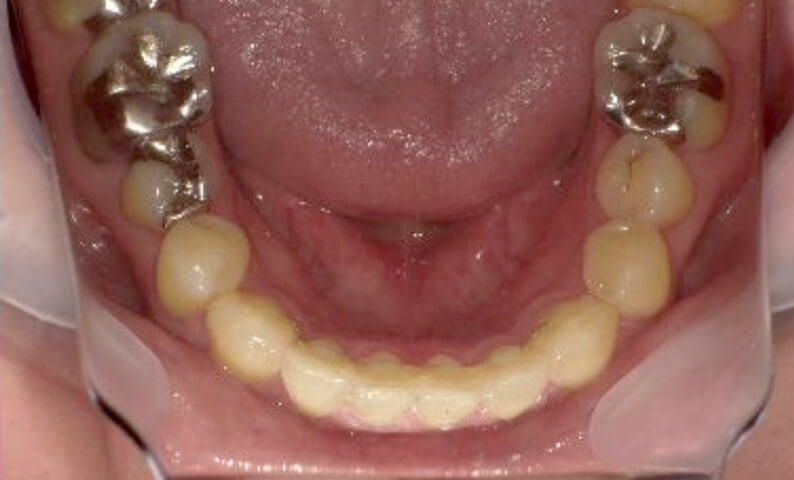

症例_003 下顎だけの部分矯正

治療期間:10ヶ月金額:24万円+税女性前歯のガタガタ下の前歯だけ上顎は補綴治療中

| Before | After |